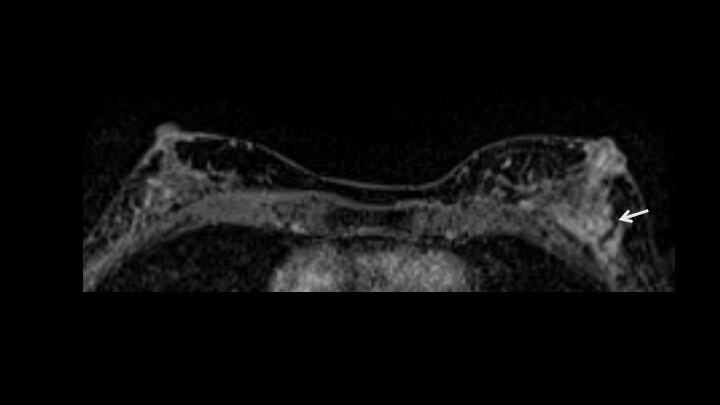

6. 造影後高分解能T1強調画像

内部造影効果 clustered ring enhancementが疑われる。右下:clustered ring enhancementのシェーマ